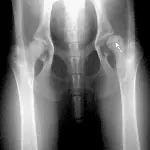

A radiograph displays the pelvic region of a canine, highlighting the hip joints and femurs. An arrow points to a notable area of concern, indicating potential dysplasia or other abnormalities in the hip structure.

Figure 2A. The capital physis of this dog, which presented with hip pain, appears slightly widened.

Figure 2B. If the patient is positioned in a frog-legged position, the hairline fracture displaces and is easily diagnosed.